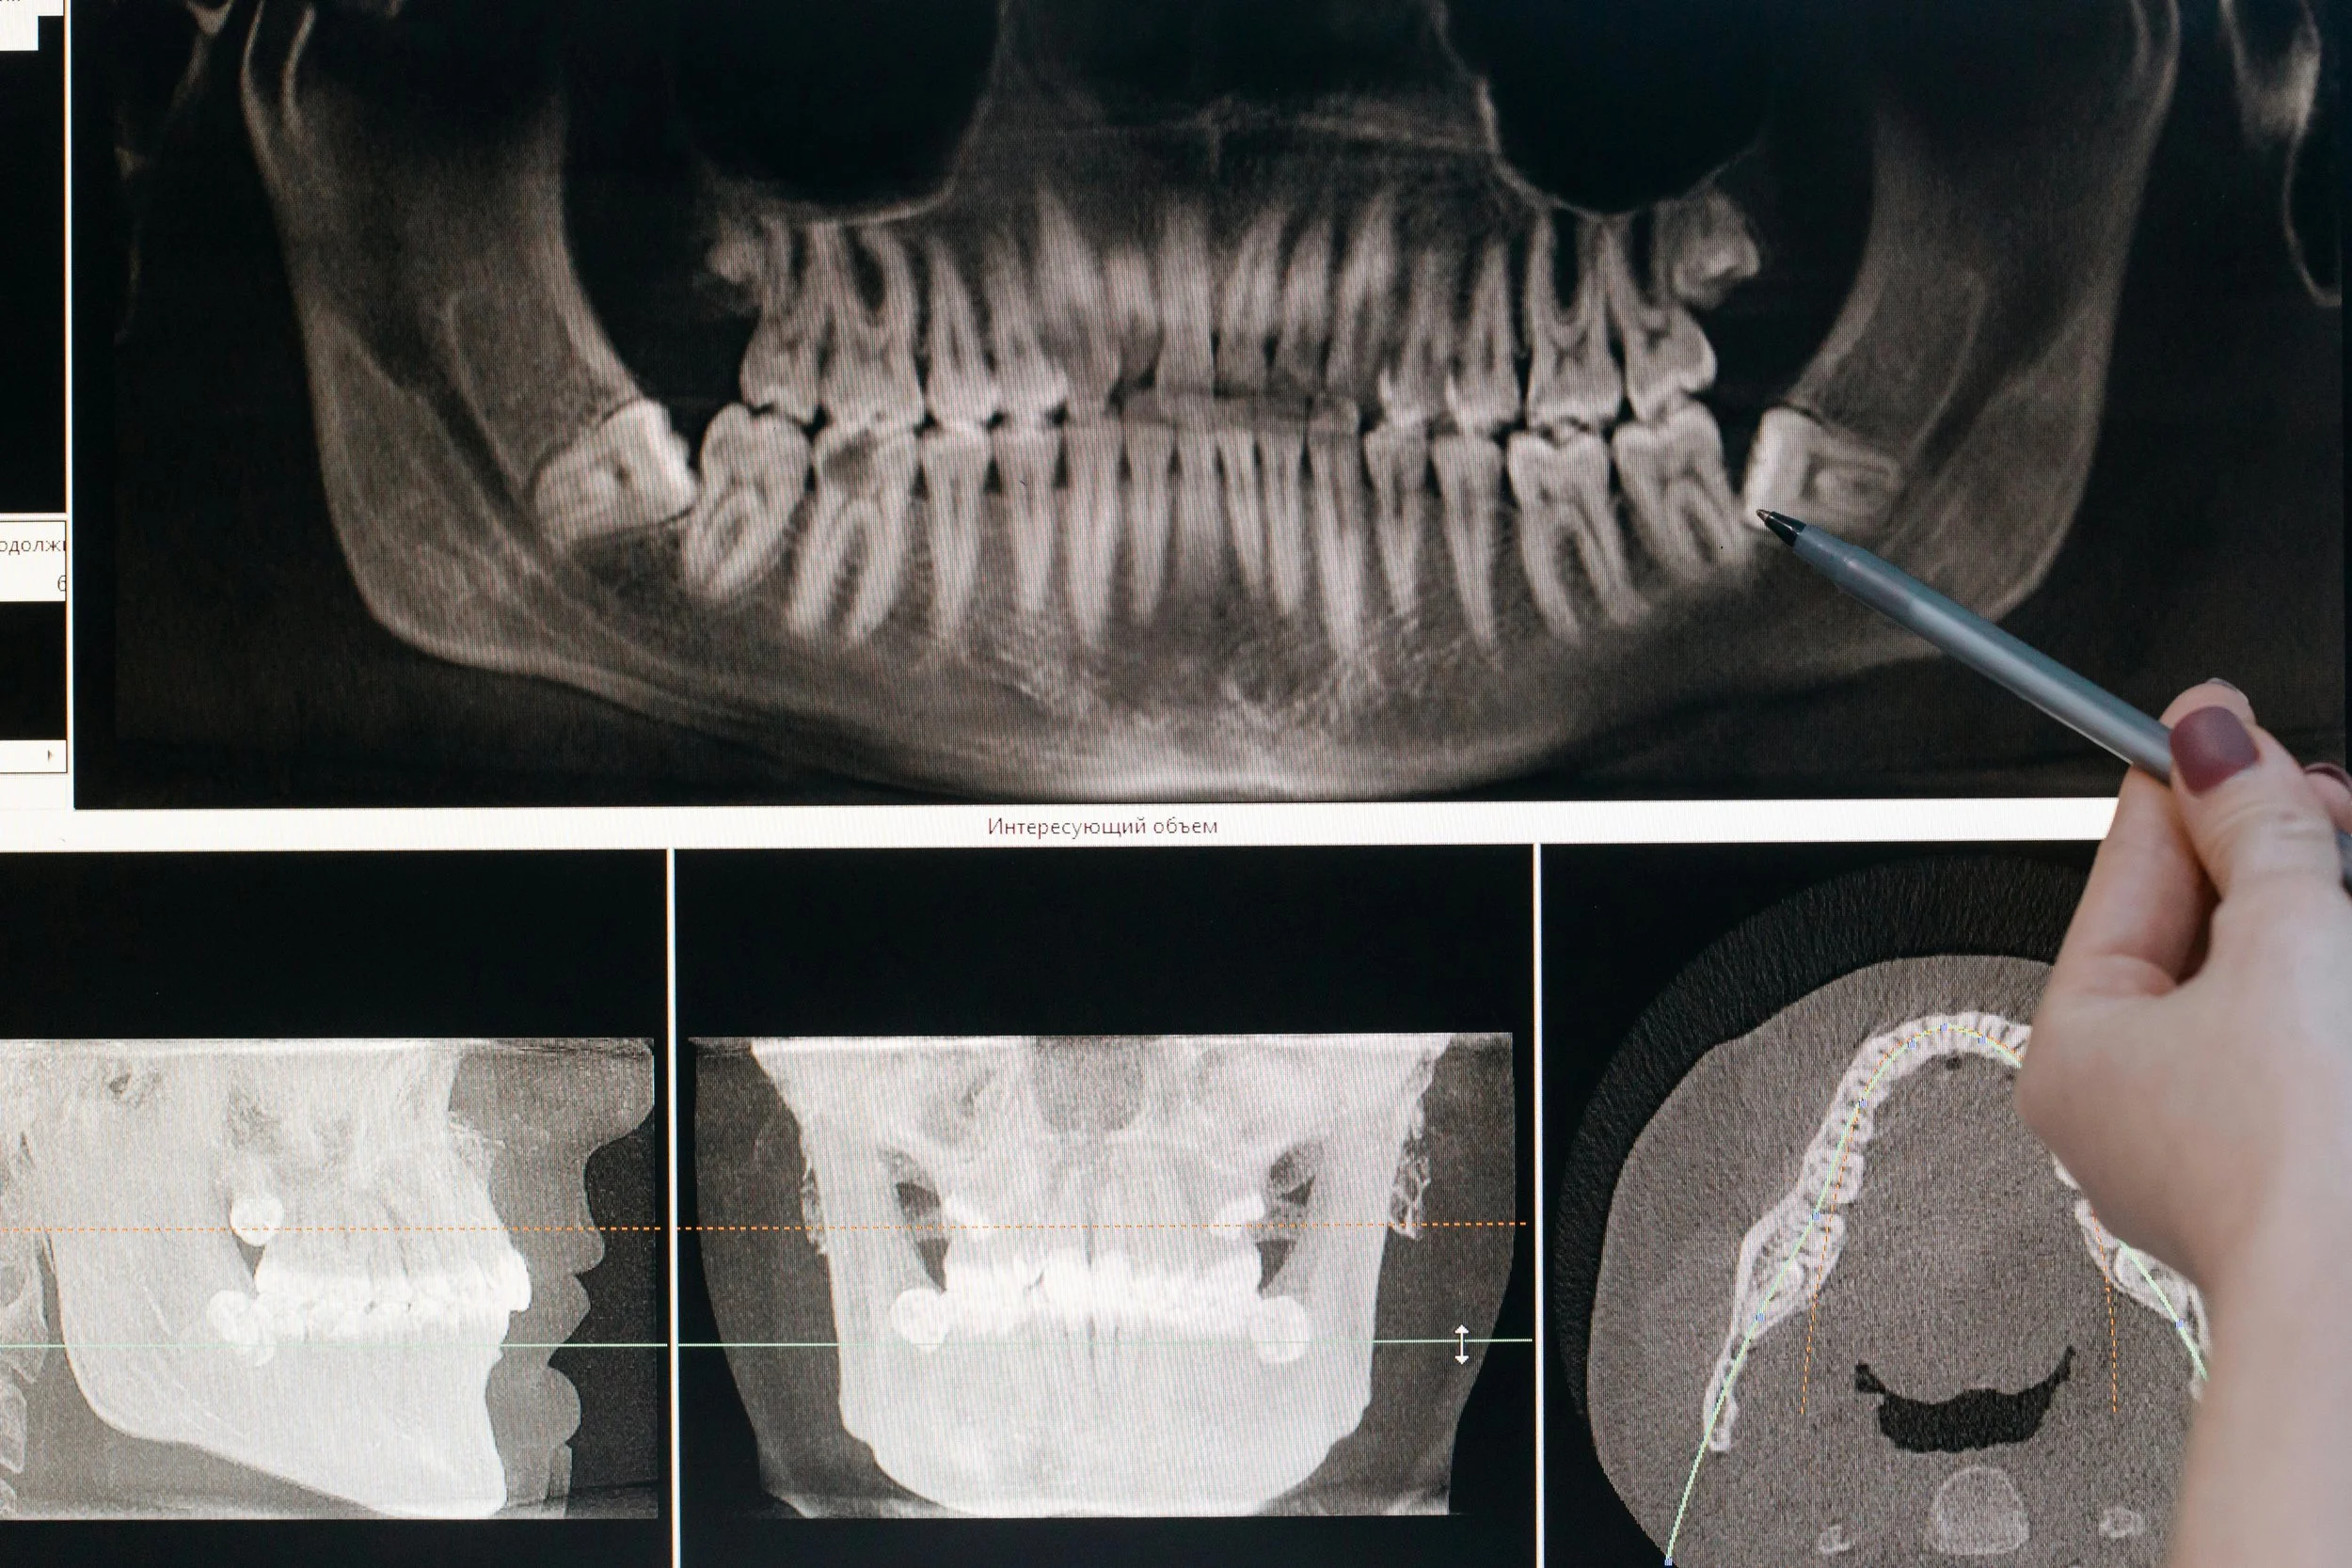

A pen being used to point to an area of a dental xray

Extracting Your Wisdom Teeth

Here at Arena Dental, we sometimes recommend wisdom tooth extraction as a preventative measure to keep your smile healthy. Impacted wisdom teeth can push other teeth out of alignment, causing ongoing pain and making them difficult to keep clean. This can lead to tooth decay and gum disease. If we see that your wisdom teeth are impacted or partially erupted, we may recommend extracting them to keep your smile healthy. The procedure is typically quick and easy, and our team will make sure you’re comfortable throughout.